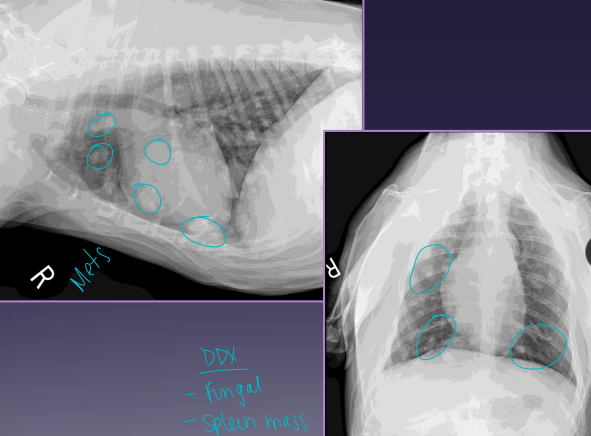

Splenic Neoplasia

Et: VERY common!

Malignant: hemangiosarcoma HSA (#1), fibrosarcoma, liposarcoma, MCT

Dt: Abd rads (mass effect, effusion, metastasis), US (mixed echotexture, cavitated lesions, enlarged spleen), biopsy

Xray chest for mets!